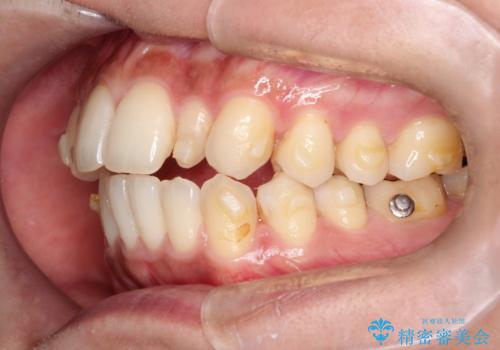

【インビザライン】矮小歯を有する方の矯正治療

- 前歯の凸凹を主訴に来院されました。

元々、歯が小さかったため矯正終了後にセラミックにて修復治療を行う治療計画をたてインビザラインにて治療を行いました。

今回はスペースを作るために歯列の拡大をメインでおこなっています。